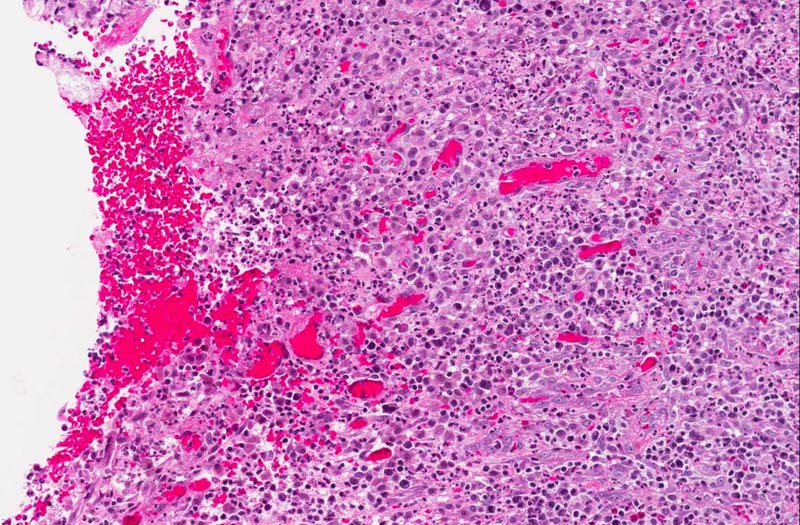

Hematoxylin & eosin

Area 3: The ulcerated area is lined by a mixture of chronic inflammatory cells including lymphocytes and plasma cells. Also present is formation of new blood vessels.